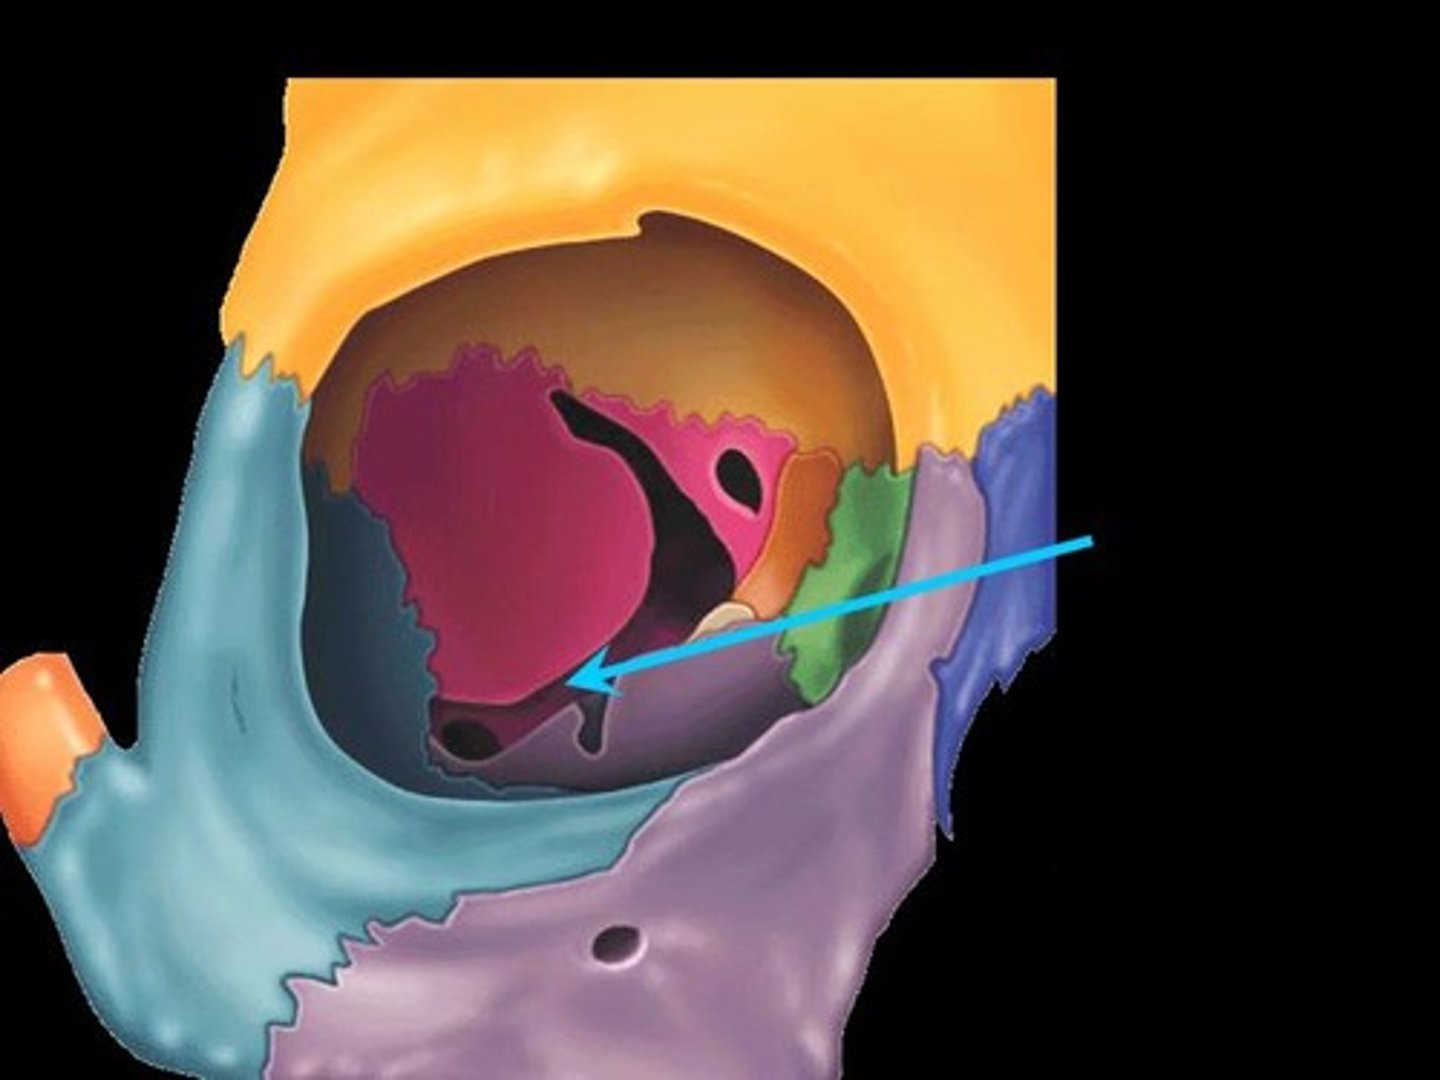

lateral ventricle

A complexly shaped lateral portion of the ventricular system within each hemisphere of the brain.

anterior horn of lateral ventricle

located in the frontal lobe and is the part of the lateral ventricle that lies in front of the interventricular foramen

body of lateral ventricles

located in the parietal lobe, situated between the anterior and posterior horns.

inferior horn of lateral ventricle

located in the temporal lobe of the brain. It is the largest of the three horns and extends from the atrium, curving anteriorly and inferiorly to go under the thalamus and into the temporal lobe

posterior horn of lateral ventricle

located in the occipital lobe of the brain, projecting backward. It is the most posterior part of the C-shaped lateral ventricle and lies deep within the occipital lobe.